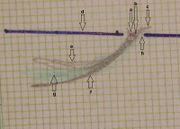

| 17:55, 15 February 2022 | Assiografia sn.jpg (file) |  |

75 KB | Admin | == Dettagli == {{CF | Descrizione = Left Axiographic traces performed with paraocclusal clutches (003) in a healthy subject. <br> a) Condylar rotation center; <br> b) Phonetic area; <br> c) Laterotrusive condylar tracking; <br> d) Orbital-axis plane; <br> e) Protrusive condylar tracking; <br> f) Mediotrusive condylar tracking; <br> g) Mediotrusive functional area of the masticatory cycles; <br> h) Laterotrusive functional area of the masticatory cycles | Fonte = {{SF}} | Data = | Autore =... | 1 |

| 17:55, 15 February 2022 | Assiografia dx.jpg (file) |  |

73 KB | Admin | == Dettagli == {{CF | Descrizione = ''Right Axiographic traces performed with paraocclusal clutches (003) in a healthy subject. <br> a) Condylar rotation center; <br> b) Phonetic area; <br> c) Laterotrusive condylar tracking; <br> d) Orbital-axis plane; <br> e) Protrusive condylar tracking; <br> f) Mediotrusive condylar tracking;<br> g) Mediotrusive functional area of the masticatory cycles; <br> h) Laterotrusive functional area of the masticatory cycles | Fonte = {{SF}} | Data = | Autore... | 1 |